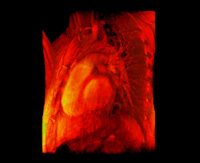

- A 4D heart dataset comprising multiple 3D volumes iterated over time. These were obtained from a phase-contrast MRI scanner. The 80MB dataset was contributed by the Department of Radiology at the Stanford School of Medicine and Lucile Packard Children's Hospital. Each volume consists of 256x256x32 16-bit samples.

- 4D heart, 1D transfer function, slice-based rendering

- 4D heart, 1D transfer function, ray-casting